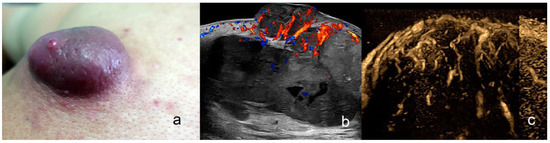

1.3.2. Squamous Cell Carcinoma (SCC)

Primary SCC Tumor

| Squamous Cell Carcinoma | hypoechoic, crumpled, wavy or irregular epidermis, convex, concave flat, bulging or fusiform shape, irregular borders | intermediate degree |